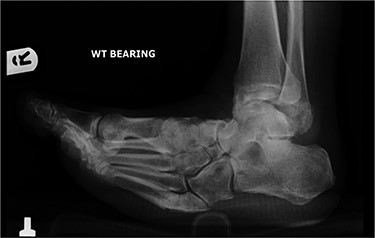

In May 2015, he had a complex midfoot reconstruction, but his foot continued to drift into varus. This was complicated by an infected ulcer on the lateral aspect of midfoot (Fig. 3). Wound infection progressed to osteomyelitis, and in May 2018, he had a hindfoot reconstruction with fusion of tibiotalar and subtalar joints using a Cerament-V-coated hindfoot nail (Figs 4 and 5).

Anterior–posterior radiograph of right ankle demonstrating tibiotalocalcaneal fusion using a hindfoot nail and screws.